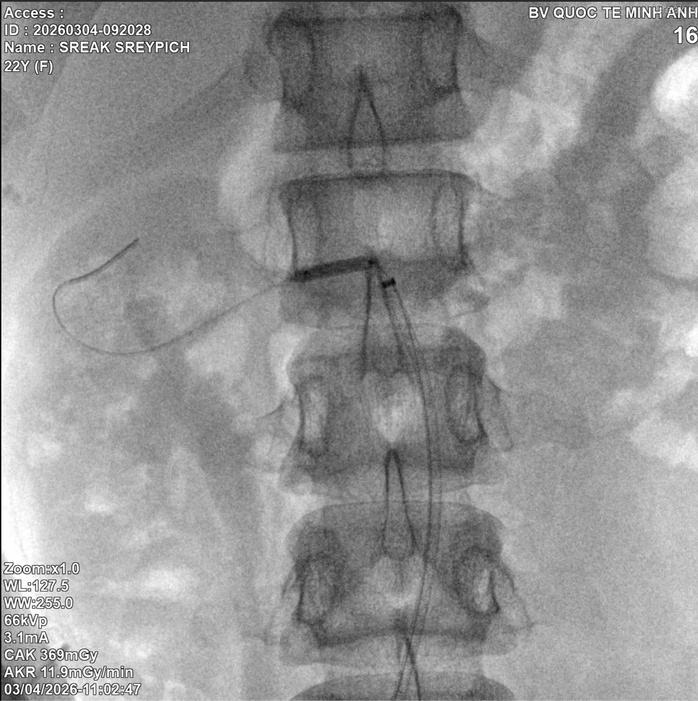

Trước tình thế "còn nước còn tát", BS Hưng và ê-kíp đã quyết định can thiệp nong và đặt stent động mạch thận phải ngay lập tức. Mục tiêu duy nhất là tái lập dòng chảy để cứu lấy chức năng của quả thận cuối cùng. Ca phẫu thuật đã thành công. Mừng vì đã giữ được hy vọng cho nữ sinh nhưng tiếc vì giá như em được tầm soát mạch máu sớm hơn từ 5 năm trước thì kết quả điều trị sẽ tốt hơn.